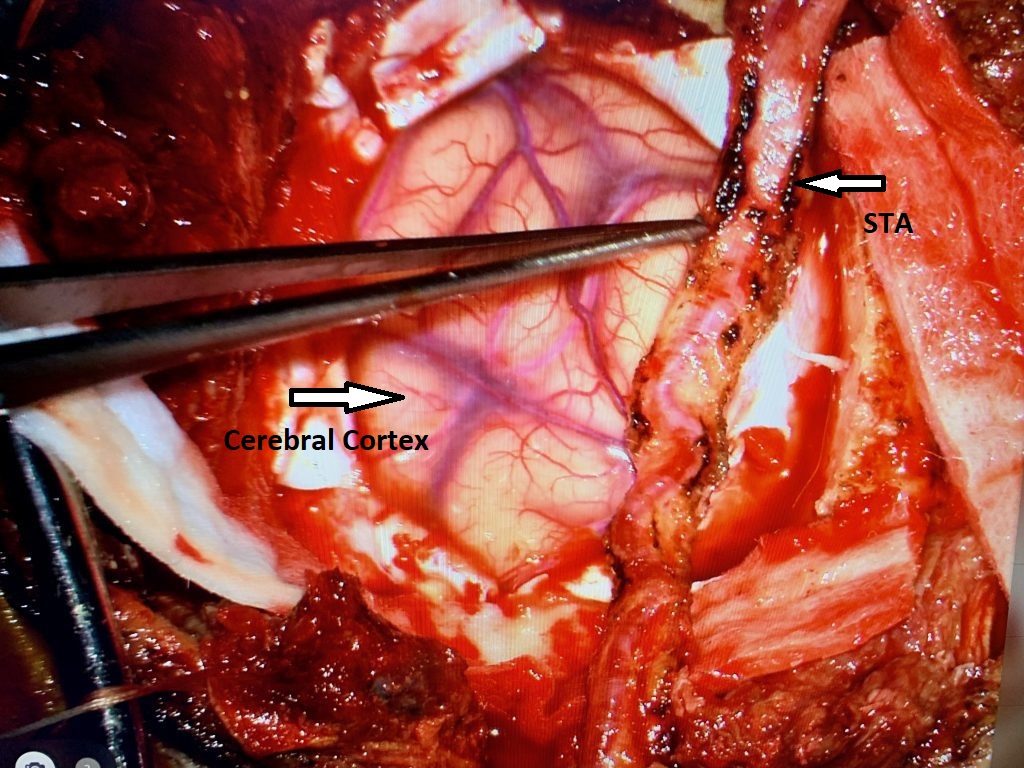

Neurosurgeons Collaborate to Treat Giant Symptomatic Meningioma

Author: Ramin Rak M.D., F.A.A.N.S., F.C.N.S., Jonathan L. Brisman M.D., F.A.C.S., Read More!